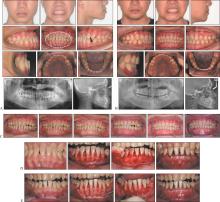

隐形矫治技术发展20多年,已从单纯的牙齿排齐工具发展为多学科口腔治疗的核心手段,尤其在牙周病正畸治疗、颞下颌关节紊乱病(TMD)正畸治疗、修复种植正畸联合治疗及正畸正颌联合治疗中展现显著优势。牙周病正畸治疗的目标是促进健康与稳定。建议牙周炎症控制后介入正畸治疗,实行轻力渐进原则,减少牙移动步距,减少隐形矫治器包裹,延长牙套替换时间。TMD正畸治疗的目标是咬合—关节协调,解除咬合创伤,稳定关节功能,排齐牙列,改善咬合。正畸介入时机仅适于稳定期TMD,强调多学科联合管理,患者正畸治疗的知情同意非常重要。修复种植正畸联合治疗的目标是空间与美学整合。隐形矫治的数字化设计可集中间隙,拓展修复种植空间,压低伸长对颌牙,直立倾斜的基牙,为修复种植提供理想的𬌗龈距离及近远中径,配合微笑设计等提升红白美学指数。严重骨性畸形的正畸正颌联合治疗可实现正畸—手术精准协同。隐形矫治数字化设计,上下牙弓宽度匹配相对固定矫治更容易实现,有效减少椅旁操作时间,提升矫治效率。目前隐形矫治在多学科领域里的应用还相对有限,高质量研究也不多,期待未来有更多高质量的研究以提高对隐形矫治的认识,让更多患者能精准高效地完成隐形矫治。

Clear aligner treatment has evolved over the last 20 years. It has transformed from a simple tool for tooth alignment to an essential component of multidisciplinary oral treatment. It has shown significant advantages in the orthodontic treatment of periodontal disease, the orthodontic treatment of temporomandibular joint disorder (TMD), integrated approaches with dental implant restoration, and the combined treatment of orthodontics and orthognathic surgery. The objective of orthodontic treatment for periodontal disease is to enhance health and stability. Commencement of clear aligner treatment is advised after the management of periodontal inflammation. The principle of applying gentle and gradual force must be adhered to. The extent of tooth movement should be reduced. The coverage of the aligner should be minimized. The time between aligner replacements should be extended. The objective of orthodontic treatment for TMD is to achieve occlusal-joint coordination, eliminate occlusal trauma, stabilize joint function, align the teeth, and improve occlusion. Clear aligner intervention is only suitable for stable TMD. Emphasis is placed on collaborative multidisciplinary management. Informed consent for orthodontic treatment of patients with TMD is crucial. The goal of combined orthodontic and restorative treatment is to integrate space and aesthetics. The digital design of clear aligners can optimize spacing, expand the area for dental implants, intrude over-erupted opposing teeth, upright tilted abutment teeth, ensure optimal gingival distance and mesiodistal diameter for dental implants, and when combined with smile design, it can significantly improve the pink and white aesthetic score. Precise orthodontic-surgical coordination is achieved for the combined treatment of severe skeletal malocclusion via orthodontics and orthognathic surgery. The digital design of clear aligners facilitates the alignment of the upper and lower dental arches more effectively compared with fixed orthodontic treatment. It effectively reduces chairside operation time and significantly improves treatment efficiency. At present, the application of clear aligners in multidisciplinary fields remains limited, and high-quality studies are lacking. We anticipate further high-quality research in the future to enhance our understanding of clear aligner treatment. This will facilitate the exact and rapid completion of clear aligner therapy for patients, resulting in aesthetically pleasing smiles.